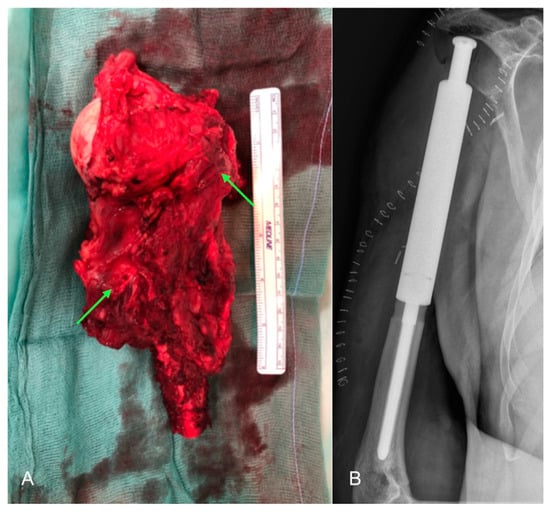

The outcome of the biopsy identified the lesion as a “bone metastasis of carcinoma with extensive areas of necrosis and sarcomatoid features, compatible with metastasis from renal cell carcinoma (immunohistochemistry: CD10+, Vimentin+, PAX8+, CKAE1/AE3+, GATA3-, CK7-, CK10-, TTF1-, p40-, p63-)”. To allow for the formulation of a correct oncological staging, the patient underwent further investigations such as cranial-brain, chest, and abdominal CT, which did not reveal suspicious findings for primary neoplastic lesions. Fluorodeoxyglucose positron emission tomography did not detect any malignant lesions. At the end of the investigations, the patient underwent surgery to resection the proximal two-thirds of the humerus (Figure 4A) and implant a mega prosthesis (Figure 4B).

Figure 4. Intraoperative image and post-operative X-ray: (A) Resection of the proximal two thirds of the left humerus with a neoplastic mass surrounding the humeral head and part of the diaphysis (green arrows); (B) postoperative antero-posterior X-ray of the left arm showing the implanted mega prosthesis.